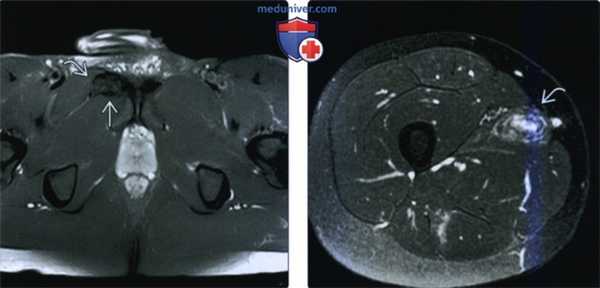

(Слева) МРТ Т2ВИ, режим подавления сигнала от жира, аксиальный срез: у наездника с ноющей правосторонней болью в паховой области определяется заметное увеличение правой длинной приводящей мышцы в области ее начала и гребешковой мышцы. Гипоксическая тендинопатия может быть проявлением дегенеративного синдрома.

(Справа) МРТ Т2ВИ, режим подавления сигнала от жира, аксиальный срез: у бегуна с усугубляющейся болью в бедре после частичного разрыва сухожильно-мышечного сочленения длинной приводящей мышцы, который был диагностирован на МРТ за четыре недели до исследования, определяется организующаяся гематома. создающая масс-эффект в области длинной приводящей мышцы.г) Патология: